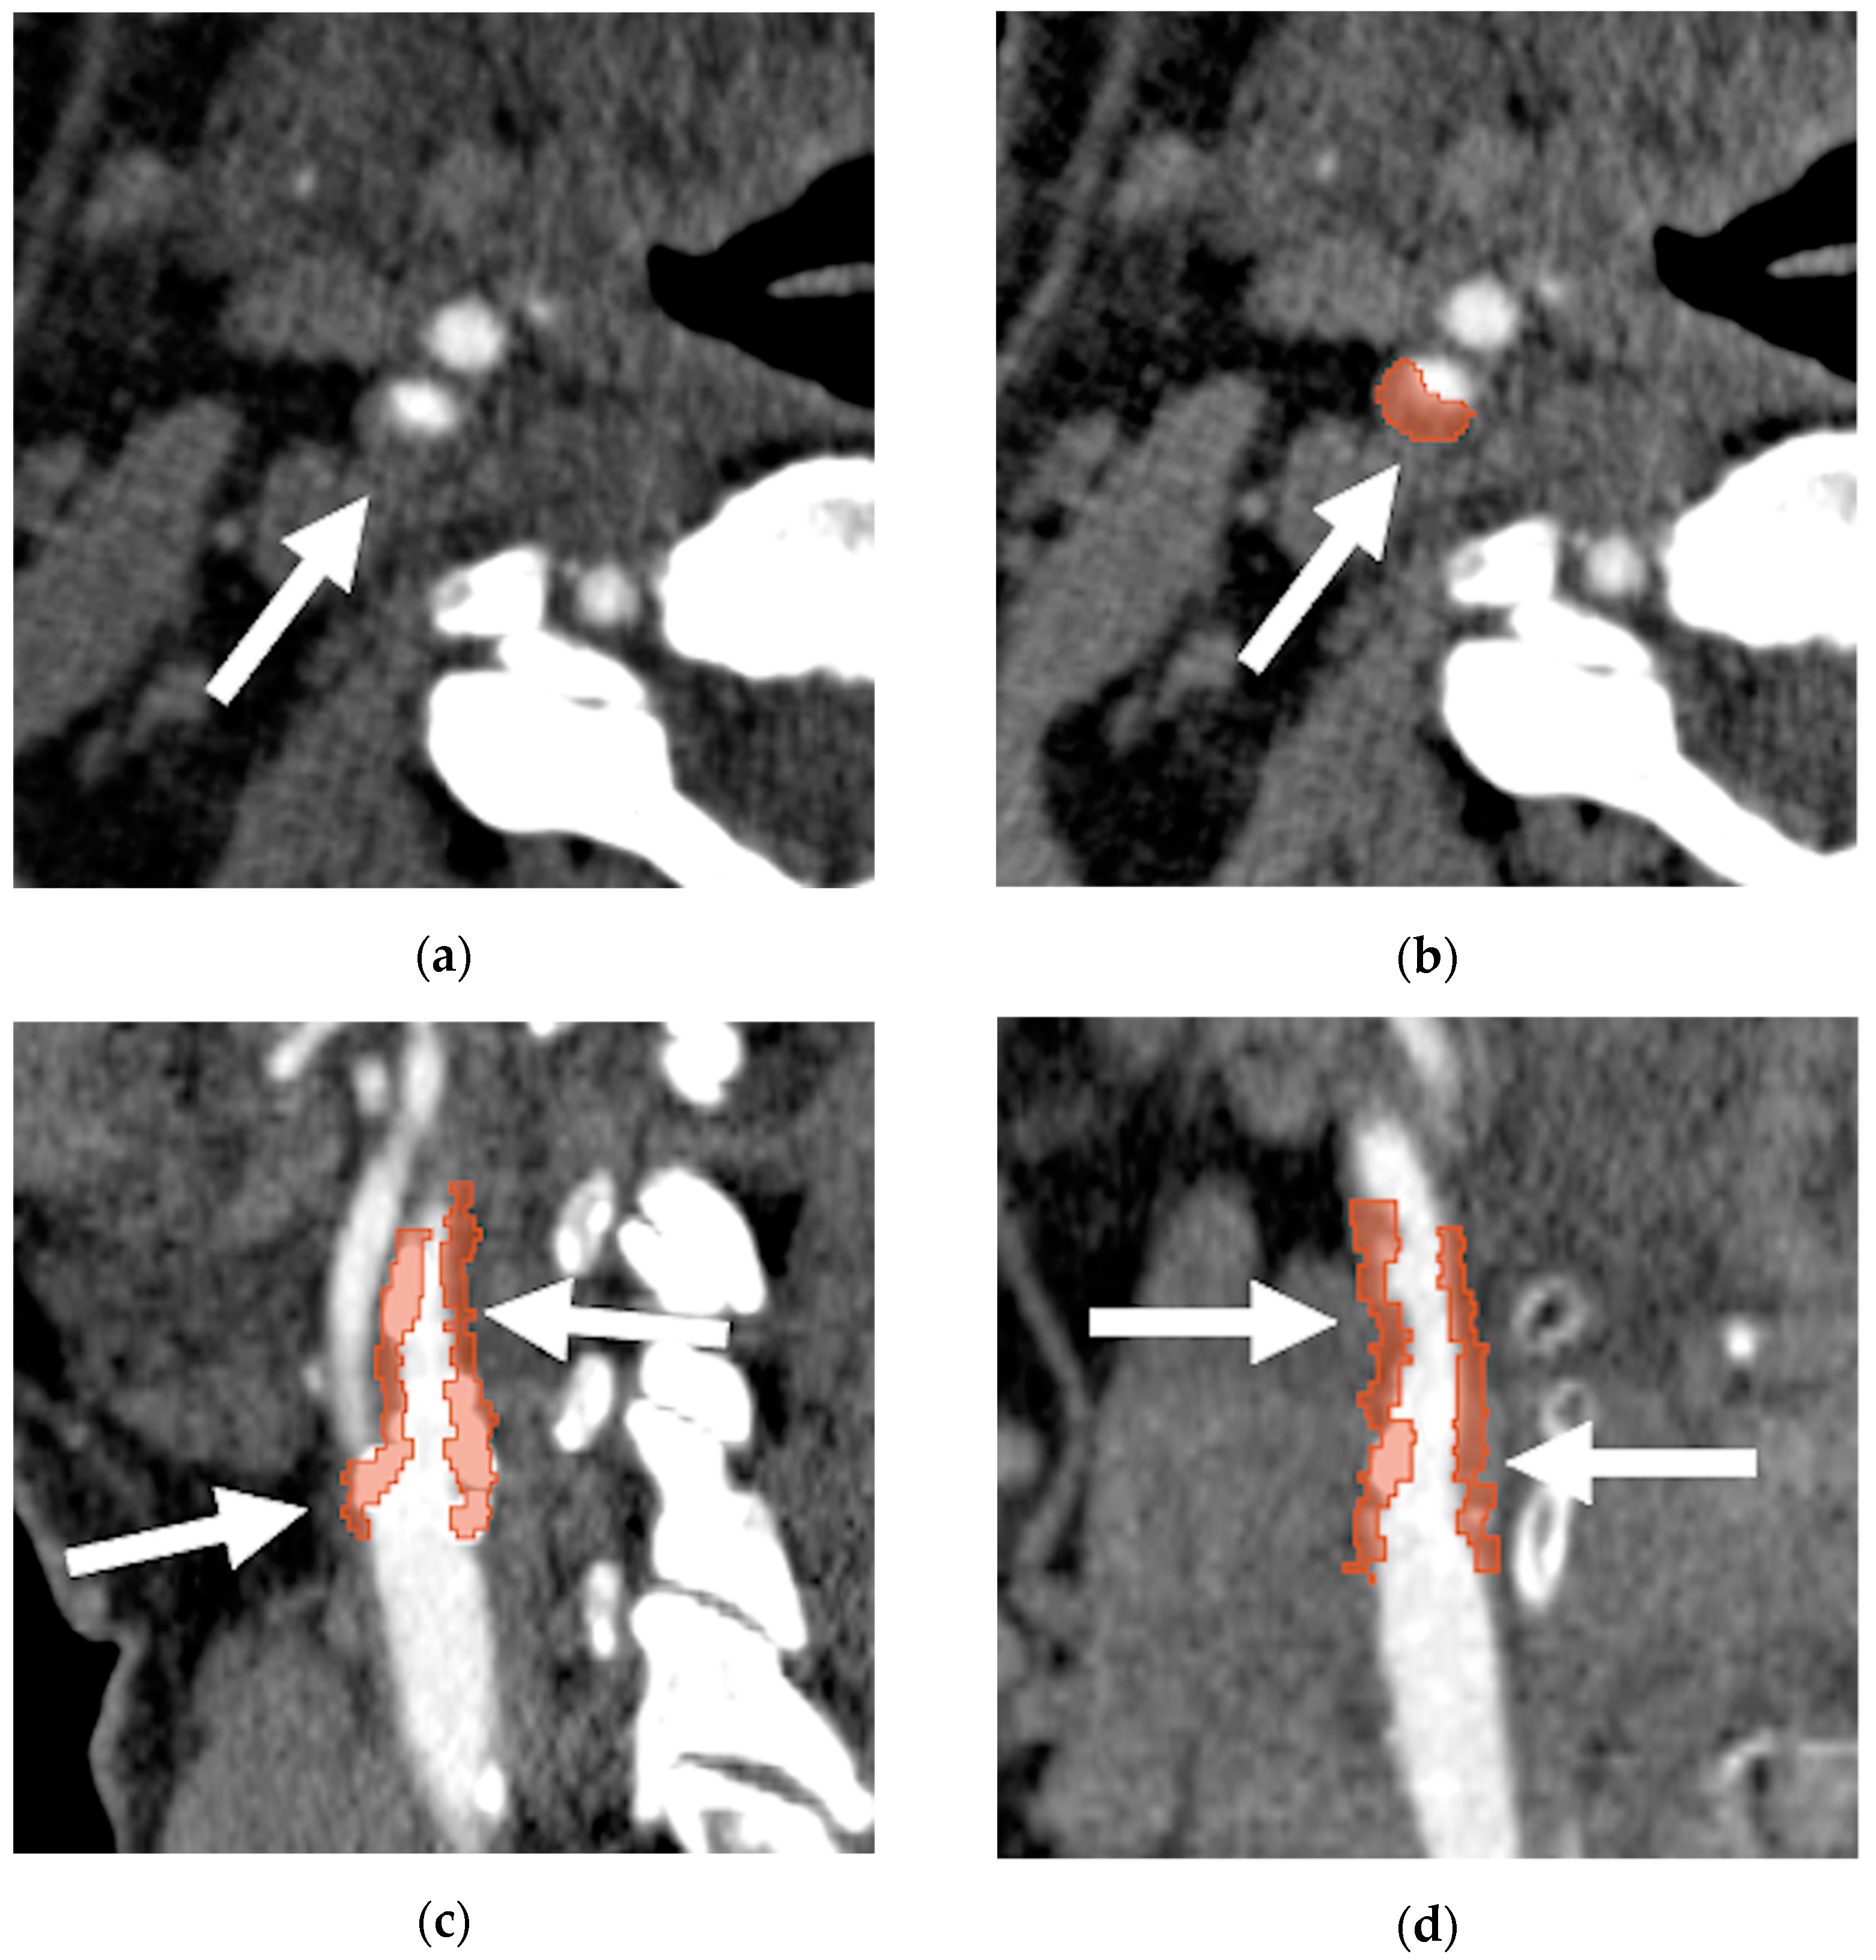

2.4. Imaging Assessment